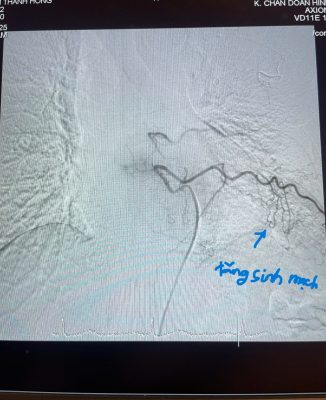

BỆNH VIỆN ĐA KHOA AN GIANG ĐIỀU TRỊ THÀNH CÔNG CA NGƯNG TIM DO TĂNG KALI MÁU NẶNG

Ngày 20/01/2025, Bệnh viện Đa khoa An Giang tiếp nhận bệnh nhân nữ tên V.T.N.H. [...]